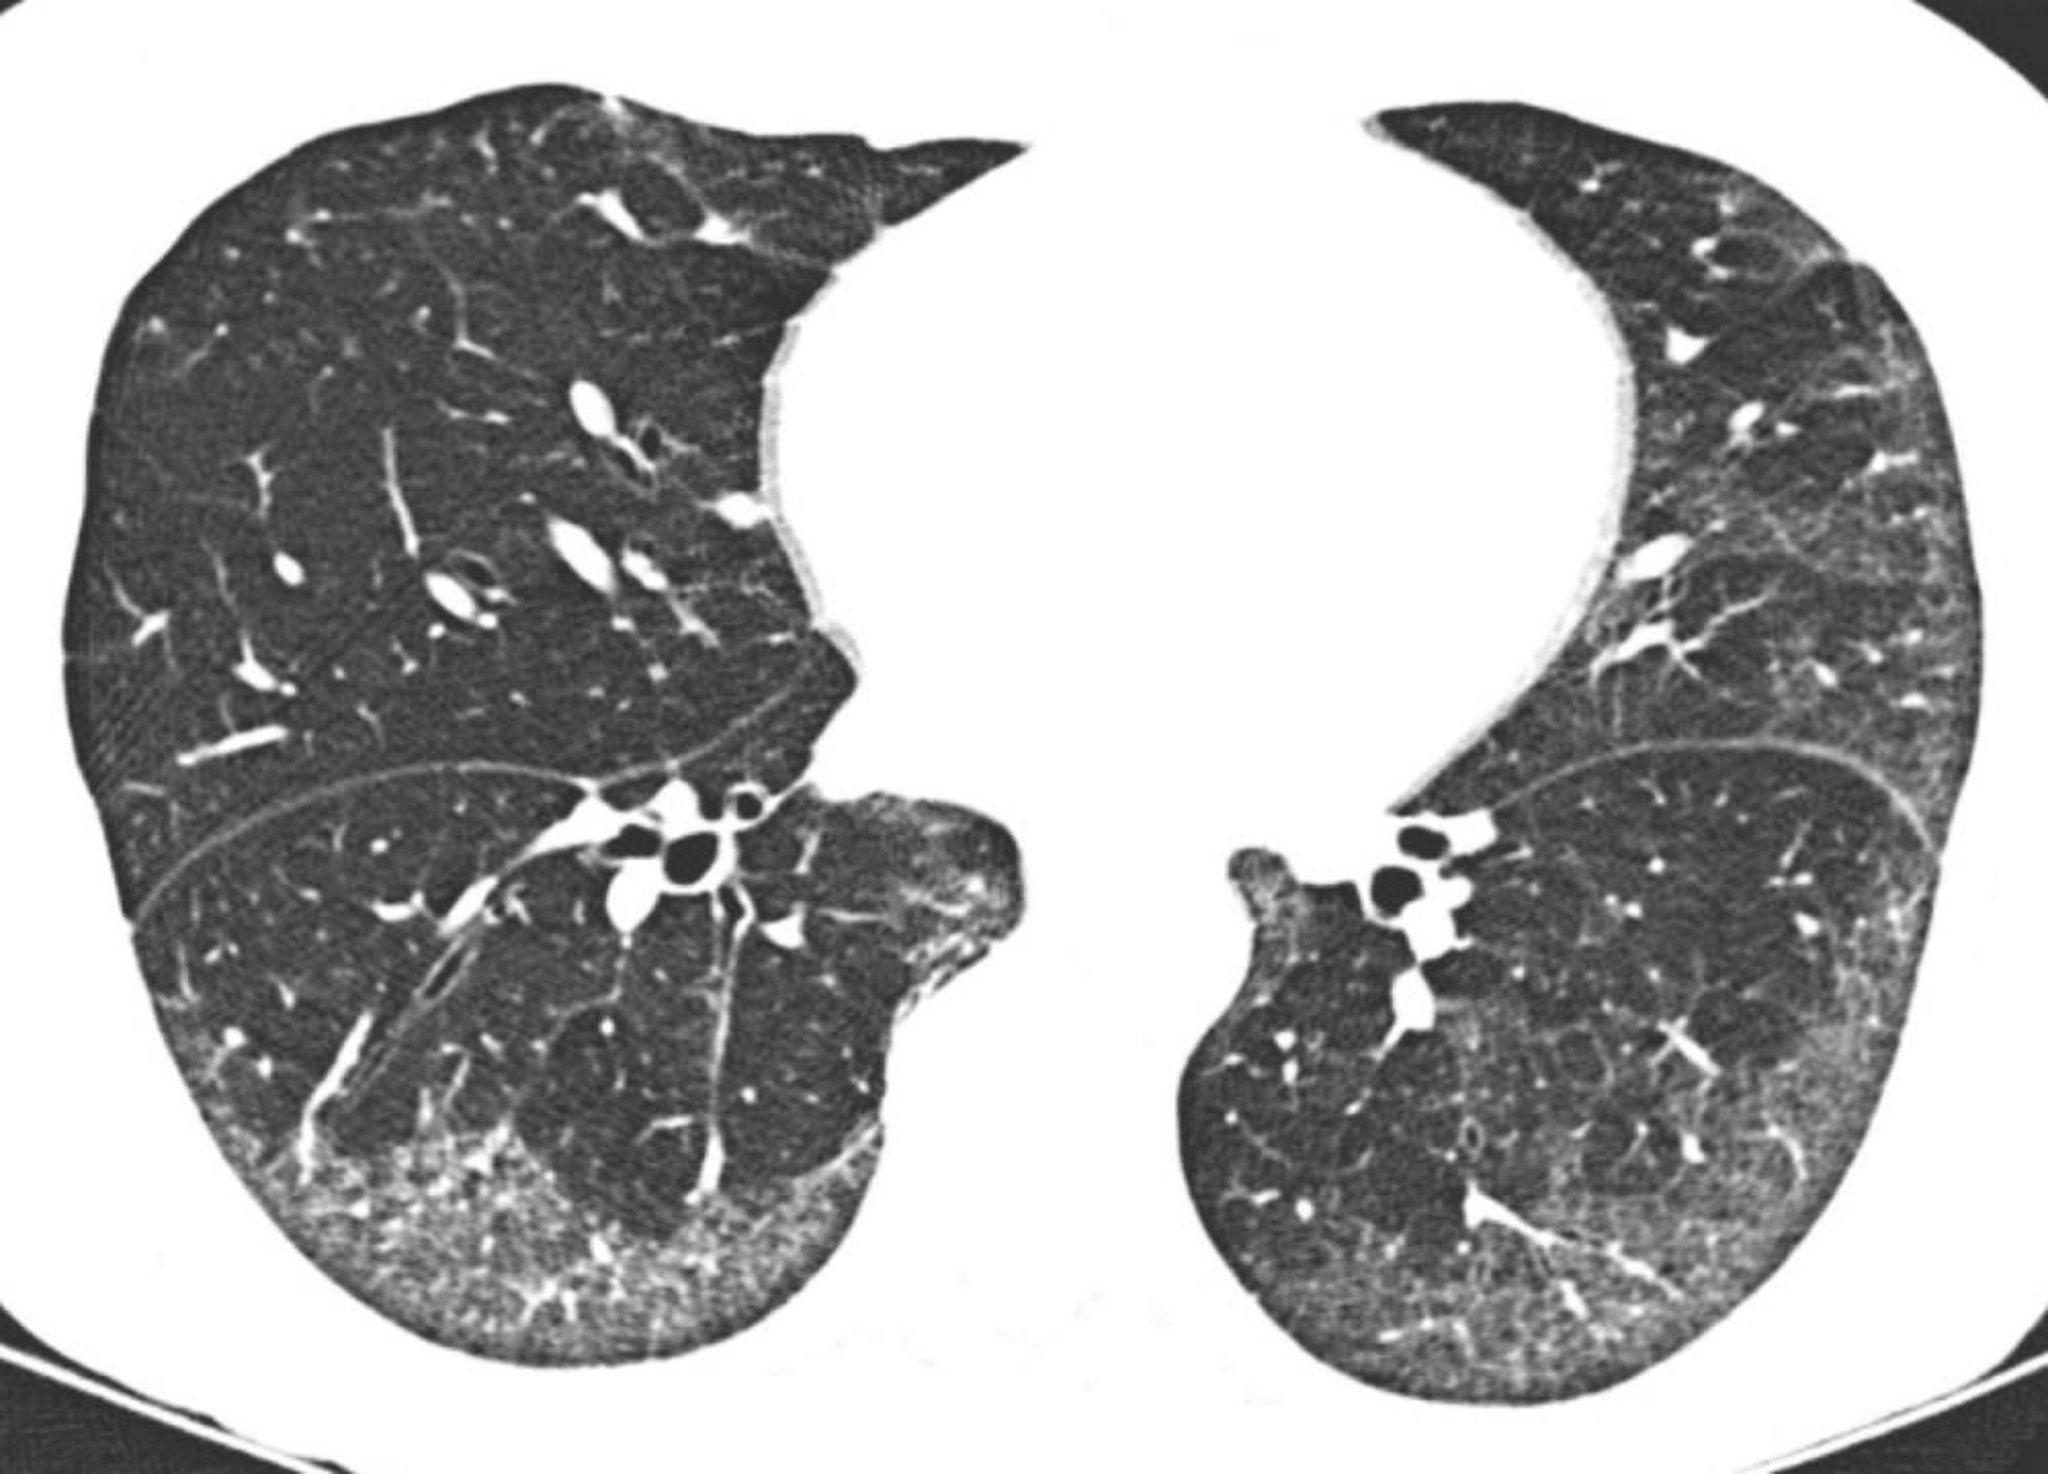

Idiopathische unspezifische interstitielle Pneumonie

Die hochauflösende CT zeigt überwiegend subpleurale und basilare Milchglastrübungen. Die relative Schonung der Lunge direkt unter den Pleuraoberflächen ist typisch für eine unspezifische interstitielle Pneumonie.

Image courtesy of Harold R. Collard, MD.